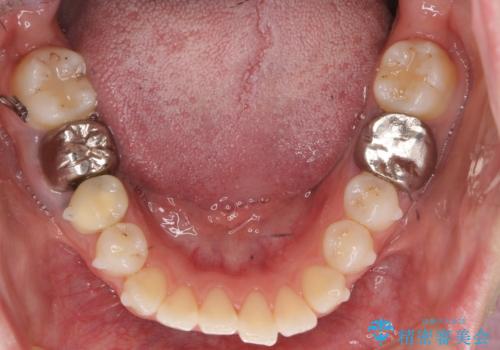

左上の犬歯が歯肉退縮しており、そこを抜歯して矯正することにしました。

右上については、奥歯をインプラント矯正により後ろに動かして、引っ込んだ前歯を並べるスペースを確保しました。